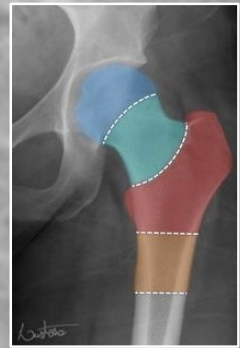

intra-capsular vs extra-capsular classification

intracapsular: involving the head or neck of femur

fracture through neck of femur (most common in younger patients)

extracapsular: involving the femur excluding head or neck of femur

fracture through the trochanters

comminuted fracture (radiolucent) of the left proximal femur

intertrochanteric fracture (between the two trochanters)

extra-capsular classification

intracapsular fracture